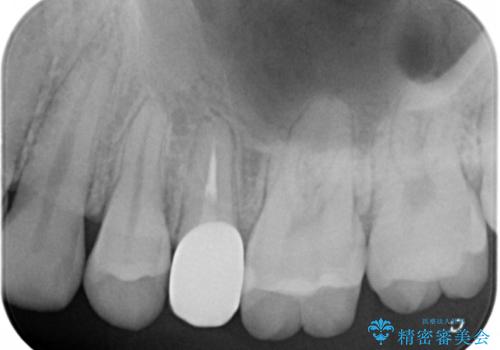

- 以前つけた被せ物がすぐにはずれてしまい1年以上放置してしまったことを主訴に来院された患者様です。

精査したところ、左上の小臼歯(左上5)は被せ物がないまま放置していたことにより、両隣の歯が寄ってきてスペースが少なくなり、また隣の歯(左上4)も虫歯になっていました。

隣の歯の虫歯治療(保険内のレジン充填)後、セラミッククラウンによる補綴を行いました。

以前つけた被せ物は1週間でとれてしまったそうで、歯ぎしりのご自覚もあることから、咬み合わせの調整を丁寧に行いました。

仮歯およびクラウンの仮付け期間を設け、はずれにくいことや咬み合わせに問題がないことを確認した上で本付けを行いました。